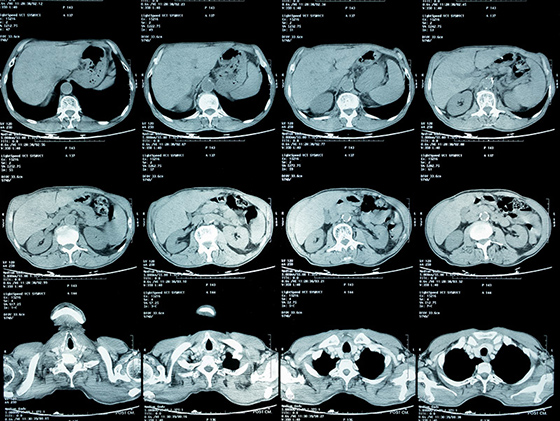

健康診断で再検査を言われ、精密検査をした結果、肺癌のステージⅣと言われました。その時は、もう何を言われたのか覚えてないですし、本当に頭が真っ白になりました。それまで、何気なく過ごしていた日常が全て失われ、何もかも嫌になりました。

それでも家族の支えもあり、少しずつ治療に前向きになり、抗がん剤治療などを受けましたが、残念ながら効果はありませんでした。副作用が強く、心も体も限界で抗がん剤治療をするくらいなら、もうステージⅣの悪性腫瘍が改善小さくなった画像を見て涙が止まりませんでした。死んでもいいと思っていました。

そんな時に私の友人から紹介され、松田先生に藁にもすがる思いで治療をお願いしました。私自身が治ることに諦めていましたが、松田先生は真摯に話を聞いてくれて、一生懸命治療をしてくれました。6ヶ月が経過した写真を見た時に、私でもわかるくらいにガンが小さくなっているのがわかりました。病院の先生の説明を聞きながら、涙を止まらなかったのを今でも覚えています。